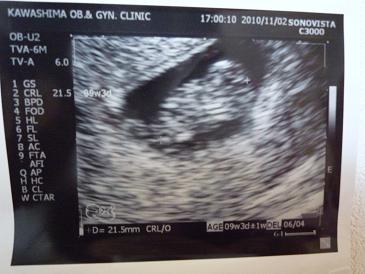

9w3dの超音波写真です。手がパタパタ動いてました。